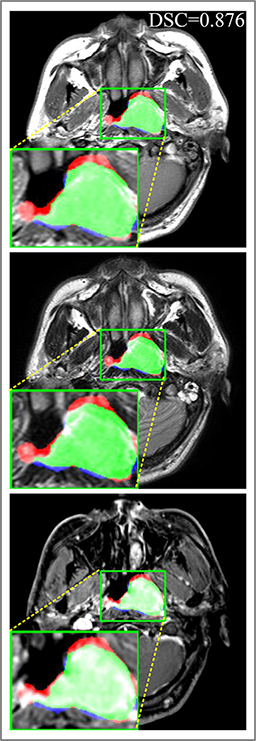

Comparison with ground truth. Some predicted results of MMFNet are shown in 2D images and 3D images in Figure 7 and Figure 8. As shown in these figures, although the shape and size of NPC are varied from each other, MMFNet can still accurately determine the regions of NPC and obtain the accurate contours of tumors. Through analyzing 2D images in figure 7, MMFNet has a capacity to fuse multi-modality MRI to reduce the confusion brought by intensity’ similarity between nearby tissues and NPC. The values of , and of MMFNet are shown in Table 1. MMFNet can reach the best results with , and .

Comparison with related works. Table 1 reports the values of , and for different methods. Predicted masks of different methods are illustrated in Figure 9 and Figure 10, which respectively present results in 2D and 3D images. Through comprehensively analyzing these results, the proposed MMFNet actually have the following properties:

Some typical predicted results of MMFNet are visualized in Figure 12. And it is worth mentioning that our proposed network is extremely time-friendly compared to manually marking by radiologists. Specifically speaking, our proposed method only needs about 9s to realize NPC delineation of a patient, while an experienced radiologist needs 10 to 20 minutes to complete it.